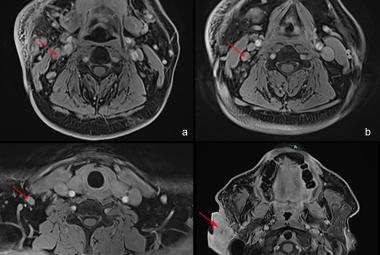

Coronavirus disease 2019 is a highly infectious disease. The complications of the disease markedly reduced after the introduction of vaccine. Thus, vaccination for COVID-19 is important and has been prompted in many countries. Reports on rare serious adverse events after COVID-19 vaccinations are well documented. The audio vestibular adverse event after COVID-19 vaccination have been reported. We herein discussed a case of labyrinthitis ossificans post COVID vaccination. A 23-year-old male presented with sudden onset right hearing loss (SNHL) with tinnitus 3 days after received COVID-19 vaccine. Pure Tone Audiometry (PTA) revealed right profound hearing loss with normal left hearing. High Resolution Computed Tomography (HRCT) of the temporal bone showed hyperdensity seen at the basal turn of the right cochlea, with Magnetic Resonance Imaging (MRI) revealed focal loss of normal T2-weighted hyperintense signal intensity of the scala tympani of the basal turn of the cochlear, suggestive of labyrinthitis ossificans. He was fitted with hearing aid and undergone for right cochlear implant for hearing rehabilitation. Labyrinthitis ossificans is commonly caused by infection and inflammation, and less commonly trauma, tumors, hemorrhage, or autoimmune inner ear disease. The correlation with vaccination is yet to be revealed and required further study.

Penyakit koronavirus 2019 (COVID-19) adalah penyakit yang sangat berjangkit. Komplikasi penyakit ini berkurangan dengan ketara selepas pengenalan vaksin. Oleh itu, vaksinasi untuk COVID-19 adalah penting dan telah digalakkan di banyak negara. Laporan mengenai kesan sampingan serius yang jarang berlaku telah didokumenkan dengan baik. Kesan otologi selepas vaksinasi COVID-19 yang secara tiba-tiba kehilangan pendengaran sensorineural (SNHL) belah kanan juga dilaporkan. Kami membincangkan kes labyrinthitis ossificans selepas vaksinasi COVID. Seorang lelaki berusia 23 tahun mengalami kehilangan pendengaran sebelah kanan secara tiba-tiba dengan kesan gigitan 3 hari selepas menerima vaksin COVID-19. Audiometri Nada Tulen (PTA) menunjukkan kehilangan pendengaran dalam yang ketara pada sebelah kanan dengan pendengaran sebelah kiri yang normal. Tomografi Berkomputer Resolusi Tinggi (HRCT) pada tulang temporal menunjukkan hiperdensiti yang dilihat pada selekoh basal koklea kanan, dengan Pengimejan Resonans Magnetik (MRI) menunjukkan kehilangan fokus intensiti isyarat hiperintens berwajaran T2 normal bagi tympani scala selekoh koklear, yang mencadangkan labyrinthitis ossificans. Beliau dipasangkan dengan alat bantu pendengaran dan menjalani implan koklear kanan untuk pemulihan pendengaran. Labyrinthitis ossificans biasanya disebabkan oleh jangkitan dan keradangan, dan jarang disebabkan oleh trauma, tumor, pendarahan, halangan vaskular arteri labirinthine, pembedahan atau penyakit telinga dalam autoimun. Hubungan dengan vaksinasi masih belum didedahkan dan memerlukan kajian lanjut.